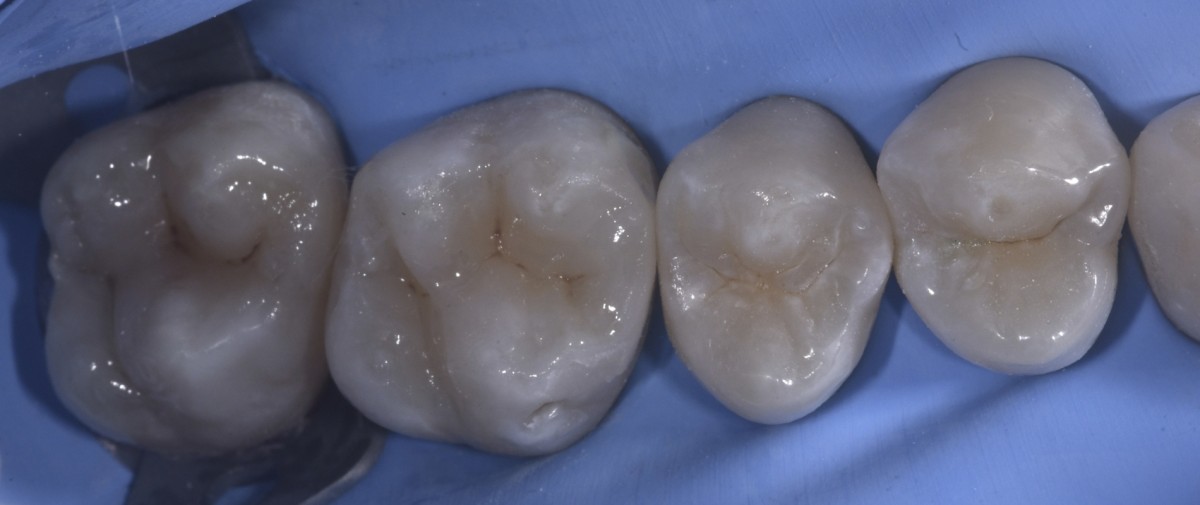

Restorations before polishing (Fig.8).